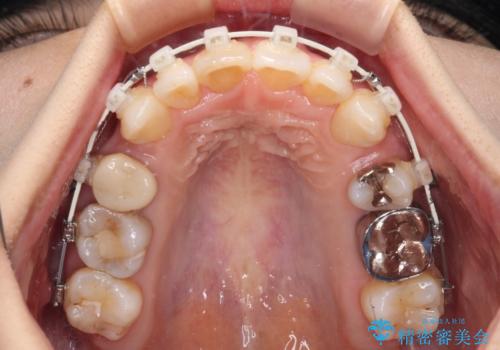

上顎左右第一小臼歯を抜去して、ワイヤー装置にて口元の突出感を改善するよう矯正治療を行うこととしました。

上顎前歯の歯軸が顕著に改善され、非常に口の閉じやすい歯列に仕上げることができました。